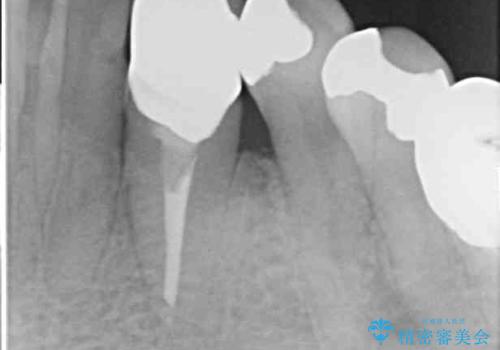

当該歯である犬歯は歯根が長く、安易に抜歯することはおすすめできないため、まずは部分矯正により歯根を引っ張り出し、その後歯周外科処置により歯槽骨や歯肉の状態を整え、最終的にはオールセラミッククラウンにて補綴治療を行うこととしました。

矯正治療中は汚れが溜まりやすく、歯肉からの出血が続きましたが、最終的には歯を保存して安定した状態で補綴治療を行うことができました。